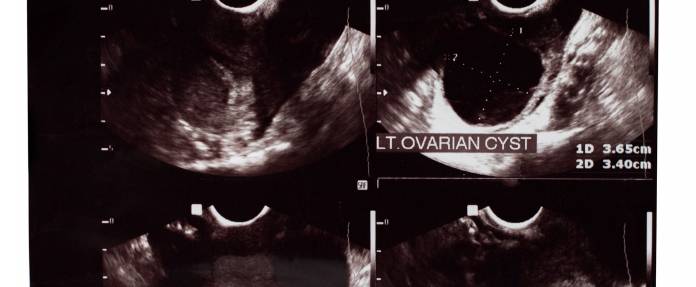

In einigen wenigen Fällen bleiben die funktionellen Zysten bestehen. Sind sie innerhalb von zwei Zyklen nicht verschwunden und weiter gewachsen, wird der Frauenarzt möglicherweise zu einer Behandlung raten. Zysten, die eine Größe von rund sechs Zentimetern erreicht haben, bilden sich kaum mehr von selbst zurück. Je größer die Zyste wird, desto höher ist auch die Wahrscheinlichkeit, dass die betroffene Frau unter Beschwerden leidet. Da eine große Zyste auf die umliegenden Organe drückt, können Unterleibschmerzen, Probleme beim Wasserlassen, Verstopfung oder Rückenschmerzen die Folge sein. Auch besteht die Gefahr einer Zystenruptur, das heißt, die Zyste kann unvermittelt platzen. Zwar ist dies meist ungefährlich, kann aber mit starken Schmerzen verbunden sein. In diesen Fällen besteht die Möglichkeit, die Zyste mit einer entsprechenden Hormongabe zum Schrumpfen zu bringen. Auch eine Entfernung mithilfe einer Bauchspiegelung (Laparoskopie) ist eine Möglichkeit.

Zysten in oder nach den Wechseljahren sollten immer genauer analysiert werden. Da im Ultraschall eine Unterscheidung zwischen gutartiger Zyste und bösartigem Tumor schwer möglich ist, werden Zysten nach dem fünfzigsten Lebensjahr meist operativ entfernt und untersucht. Bei Frauen in der Postmenopause wird auch die komplette Entfernung der Eierstöcke erwogen. Da sich Ovarialkarzinome selten durch Beschwerden bemerkbar machen, werden siebzig Prozent erst in einem späten Stadium diagnostiziert. Deshalb kann eine Ovarektomie, eine Entfernung der Eierstöcke, bei familiärer Vorbelastung eine Prophylaxe gegen Eierstockkrebs darstellen.